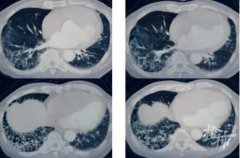

• 77岁大爷肺部变“蜂窝”!元凶竟是这些习惯

• 男子突然咳血,肺部竟成“马蜂窝”!跟他爱穿的衣服有关